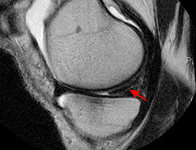

MRI scan demonstrating horizontal cleavage tear of medial meniscus (arrow); white horizontal line separates the inferior and superior portions of the torn meniscus

From the collection of Dr Kevin R. Stone